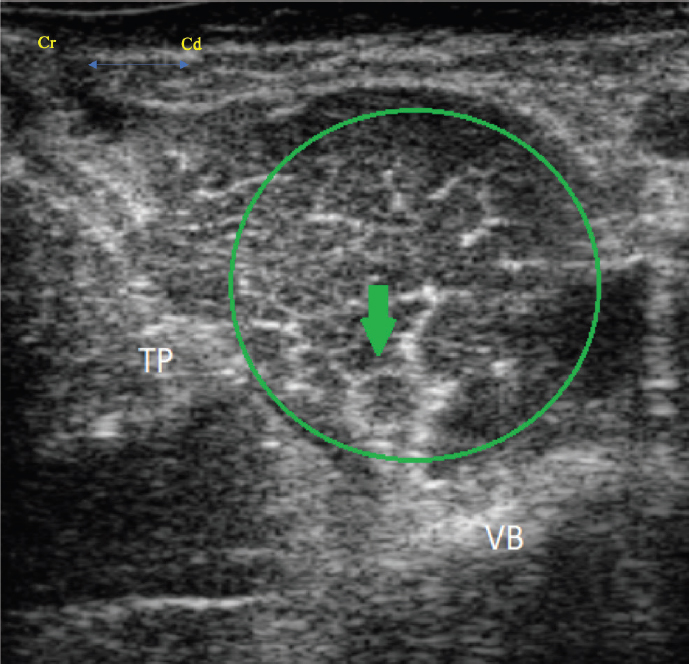

With the patient remaining in right lateral recumbency, the psoas compartment block was performed using the technique described by Tayari et al(2017). The ultrasound transducer was placed perpendicularly to the long axis of the spine just cranial to the wing of the ilium in the lumbar area, in a torso-ventral position . After visualiz ation of the IPM and the FN (a rounded hypoechoic structure with a thin hyperechoic rim), the transducer was rotated 45 ° dorsally on its short axis and oriented caudally, maintaining the ultrasound view of the IPM and FN. The FN was the only nervous structure that was possible to recogni ze in the psoas compartment and so the ON was not identified. The needle was then advanced in-plane, until it was located in close proximity to the FN (Figs. 3 and 4). The LA solution was injected after aspirating, to rule out intravascular needle placement. Correct positioning was confirmed by spread of local anesthetic around the FN .

Fig. 4. Transverse ultrasound image showing the iliopsoas muscle (green circle), the femoral nerve (green arrow), the vertebral body (VB) and the transverse process (TP). The femoral nerve appears as a rounded hypoechoic structure with a thin hyperechoic rim.